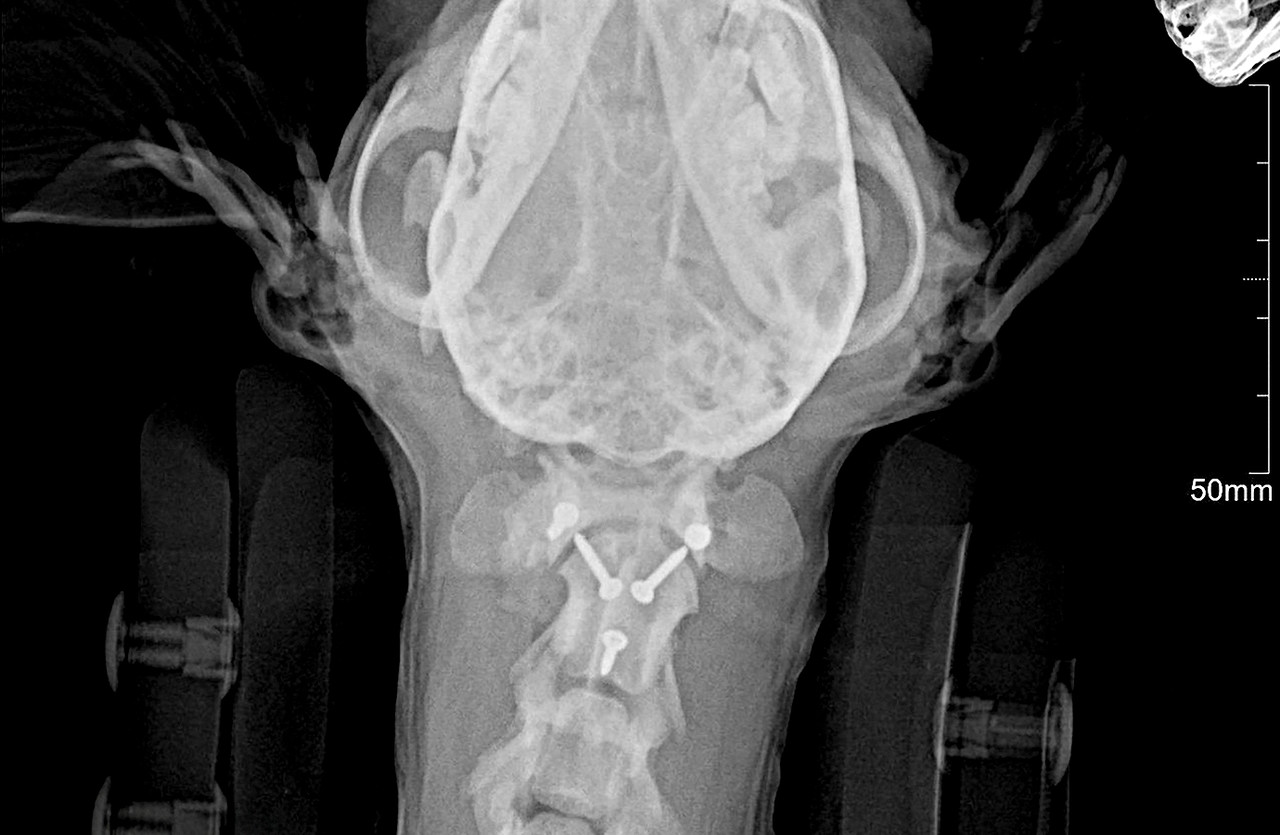

MRI, CT 등 첨단 영상 의료기기를 활용하여 정확하게 진단하고 안전하게 치료하고 있습니다.

1번 경추인 환추와 2번 경추인 축추를 합쳐서 환축추라고 부릅니다.

환축추에 문제가 발생해 불완전한 탈구가 발생하면 척수신경에 영향을 주어 통증 및 사지마비 등이 발생할 수 있습니다.